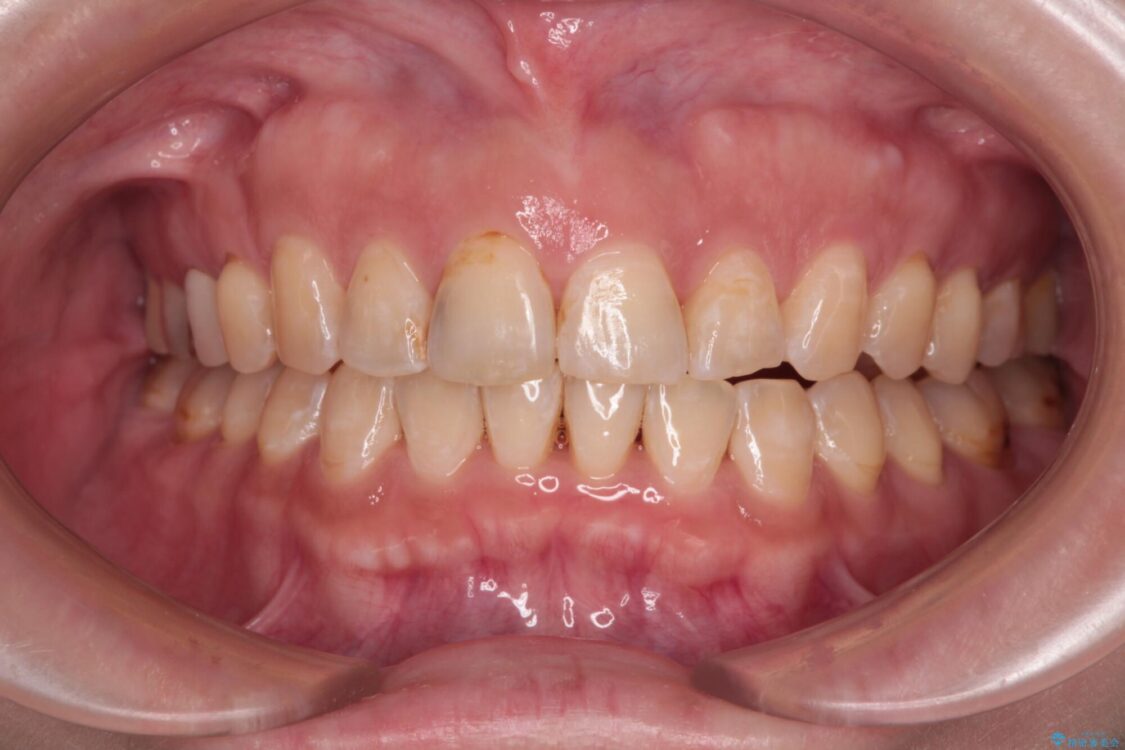

治療後について

舌の突出癖が原因で上下の歯に大きなスペースが生じていたため、舌のトレーニングをしっかり行っていただくことで、上顎歯列をスムーズに移動させることができました。

治療後

• 【モニター】飛び出た前歯を整えたい ワイヤー矯正治療 治療後画像